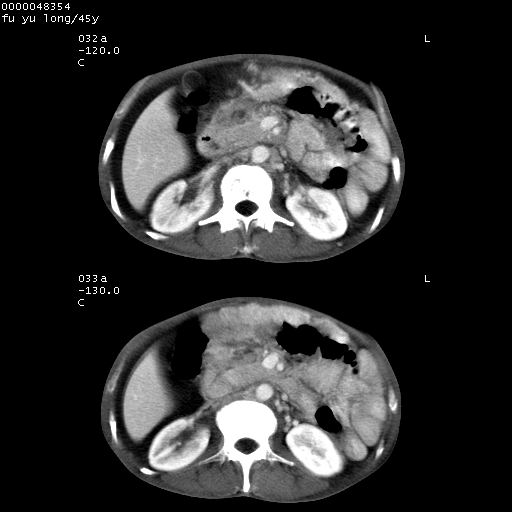

以下是引用lkc8963在2008-5-30 8:44:00的发言:[br]胃窦癌伴网膜(胃结肠韧带)/腹膜及腹膜后淋巴结转移.

以下是引用医影拾贝在2008-5-30 2:38:00的发言:[br]气肿性胃炎、胃十二指肠溃疡、腹膜炎,考虑穿孔可能性较大